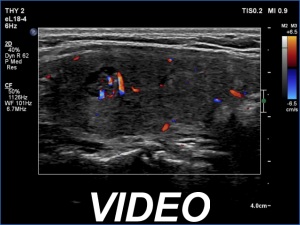

Examination 3 months later (second row of images):

Clinical presentation: The patient had no complaints.

Palpation: no abnormality.

Laboratory tests: TSH 5.87 mIU/L, FT4 8.1 pM/L, CRP 0.2 mg/L.

Ultrasonography: The thyroid has decreased in size. The echogenicity and the vascularity of the right lobe remained unchanged while those of the left lobe became almost normal.

Suggestion. Follow-up in six months.